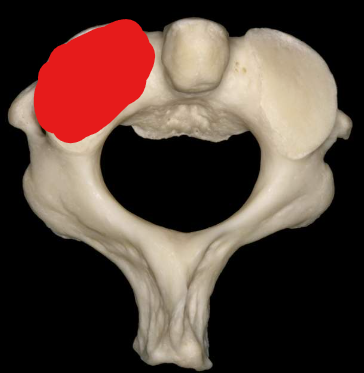

Atlas

Anterior tubercle

Anterior arch

Superior articular facet

Transverse foramen

Posterior arch

Posterior tubercle

Lateral masses